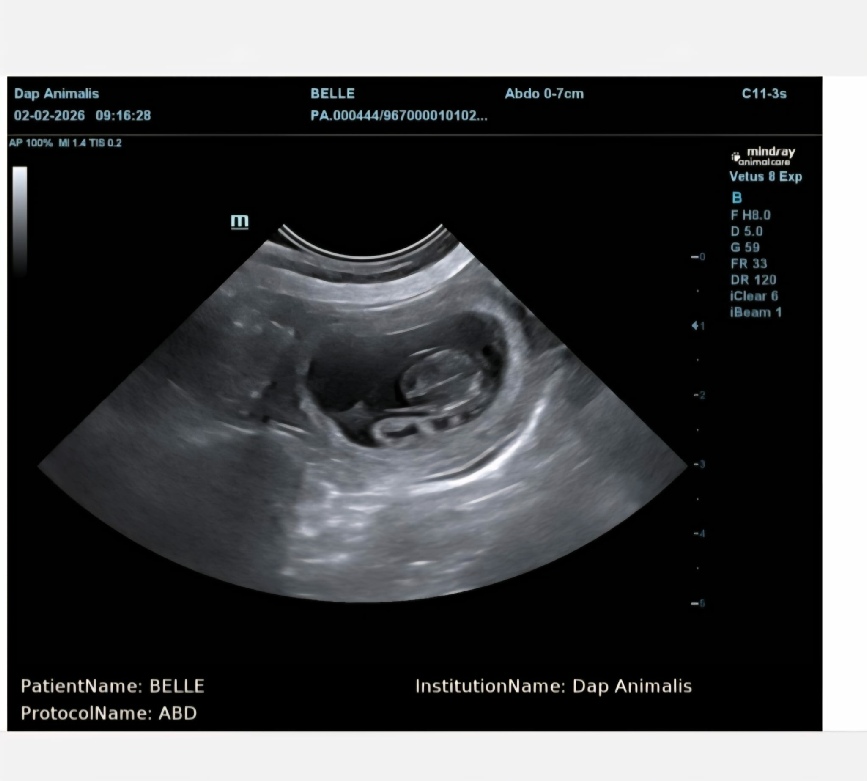

Ja hoor  op 2 februari krijgen we via de echo de bevestiging…

Belle en Silco worden mama  en papa….

Belle draagt meerdere puppies , maar hoeveel juist dat liet ze net niet zien…